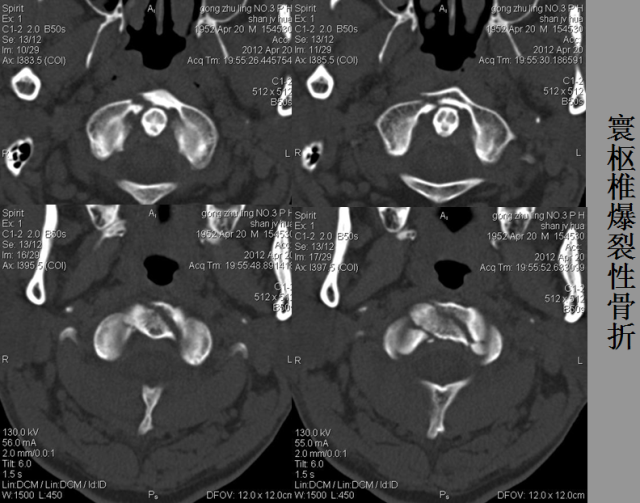

骨折篇

01

定义:骨折{Fracture}是指骨的完整性和连续性的折裂或粉碎。包括创伤性骨折、疲劳性骨折和病例理性骨折。 临床上以创伤性骨折*常见。